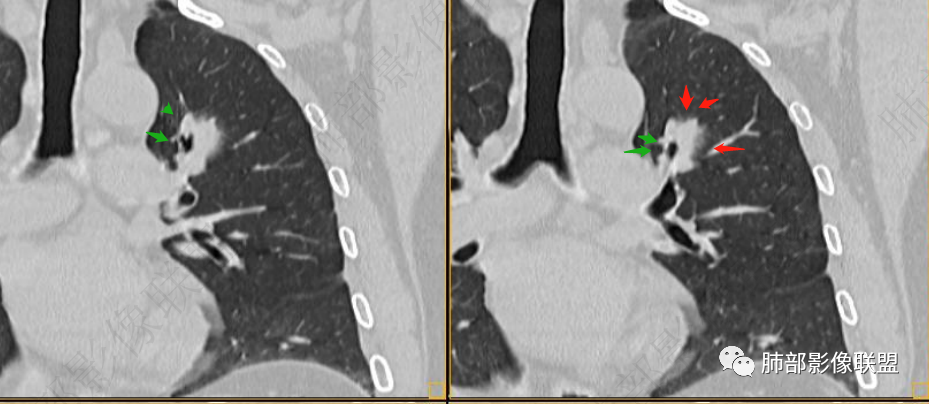

我标示一下,说一下个人的想法

1、病史上看:

57岁,属于高危人士;病灶3年逐步增大,肿瘤按理是要考虑的

初始病灶应该是这里

病灶朝前、外侧进展

病灶包括两部分

1、实性2、周围GGO

可惜没给前片连续的图

目前看支气管通畅

实性部分强化明显,边缘平直

2、病灶以实性密度为主,前、外侧蔓延,GGO部分边界清楚,部分欠清

支气管未见受明显侵犯,未见阻塞,壁增厚,狭窄或扩张。

软组织+重建;病灶实性部分不是类圆形,密度相对均匀柔和。

肺门区病灶与支气管关系不密切,强化显著、磨玻璃晕等等容易想到的是肺腺癌。而不首先考虑与支气管密切相关恶性肿瘤,如鳞癌、类癌、粘液表皮样癌等等。

1、连续3年观察,病灶逐步增大,符合惰性恶性肿瘤。2、支气管壁增厚,腔内内壁无变化——病灶长轴沿支气管周围蔓延;朝外走,内侧没有,提示病灶间质为主,与支气管无关。

3、GGO长期存在,朝外蔓延,支持恶性特点。

支持淋巴瘤的关键点:1、间质为主;2、与支气管无关;3、边缘GGO的长期存在支持恶性

因为与支气管无关不支持腺癌,还是要警惕淋巴瘤。